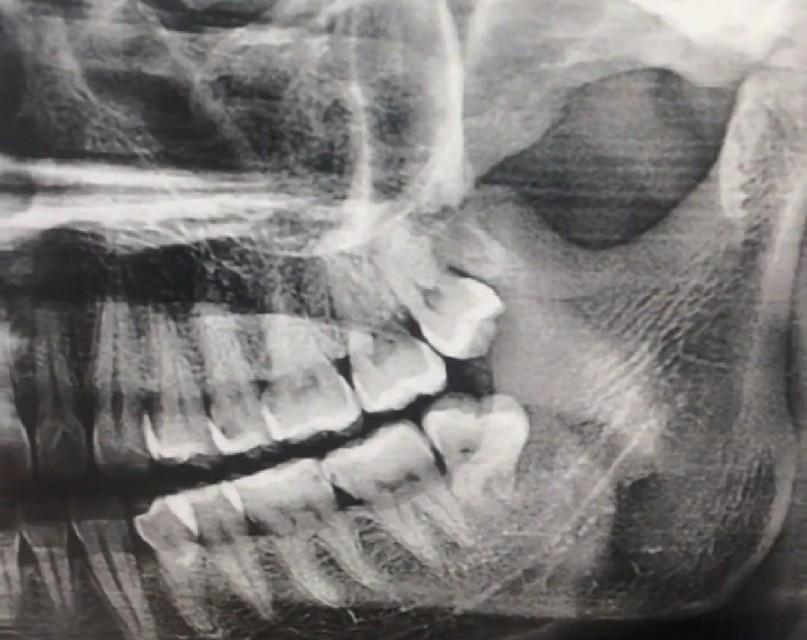

下顎的智齒拔起來可以說相當(dāng)?shù)睦щy,它有逆生長的、壓根不露頭的、還有牙根帶鉤的、關(guān)鍵是下顎接近腦神經(jīng),拔下額的智齒必須要拍牙齒圖片,拍一個圖片也就50塊錢左右,如果圖片出來智齒的位置比較麻煩,好還是多花點錢去三甲醫(yī)院拔除,下顎智齒拔除的困難度不同價格也不同,有的隱藏智齒需要開刀縫合切割,長時間甚至需要醫(yī)生一個多小時的折騰,三甲醫(yī)院的價格從800到2000也就不奇怪了。